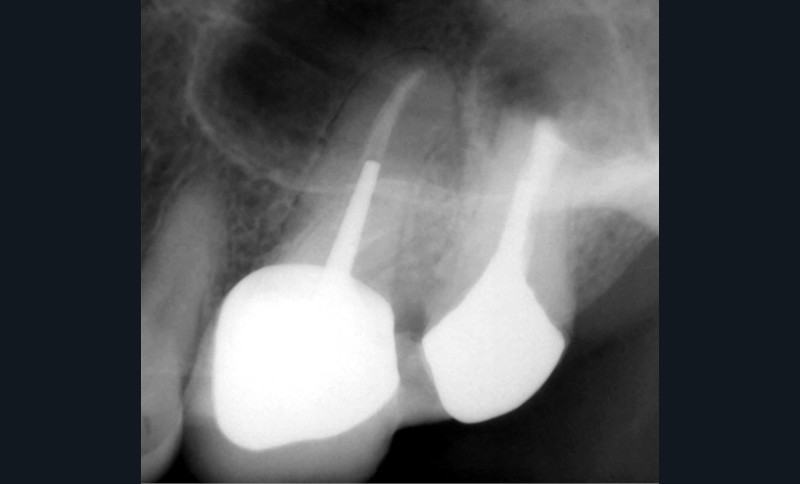

Le laser Erbium s’insère donc parfaitement dans nos principes actuels de traitements mini-invasifs comme activateur de nos solutions d’irrigation (fig. 1a à c).

Le passage du laser est répété plusieurs fois, en début, au milieu et en fin de préparation. Un protocole peut alors être proposé : 40 mJ ; 20 Hz (fig. 7). L’utilisation de biocéramiques Bioroot (Septodont) ou Total Fill R (FKG) permet de sceller le système ainsi nettoyé, en assurant une action biologique de longue durée [46] (fig. 8a à c).